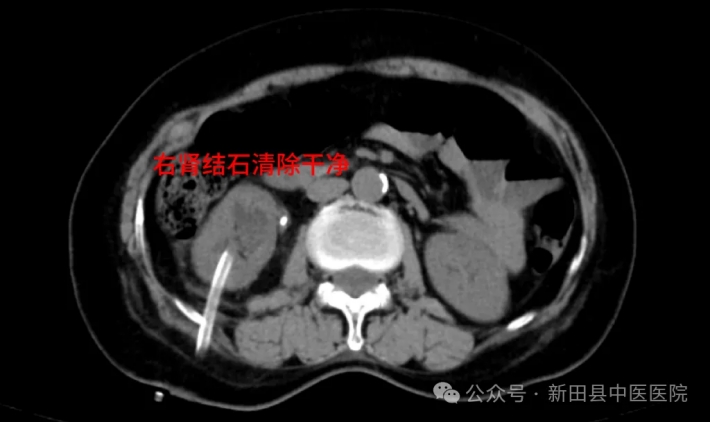

术后影像学检查提示,右肾结石清除干净。一周后,陈女士康复出院时,对邓勇军主任连声称赞。

▲术后DR

▲术后CT